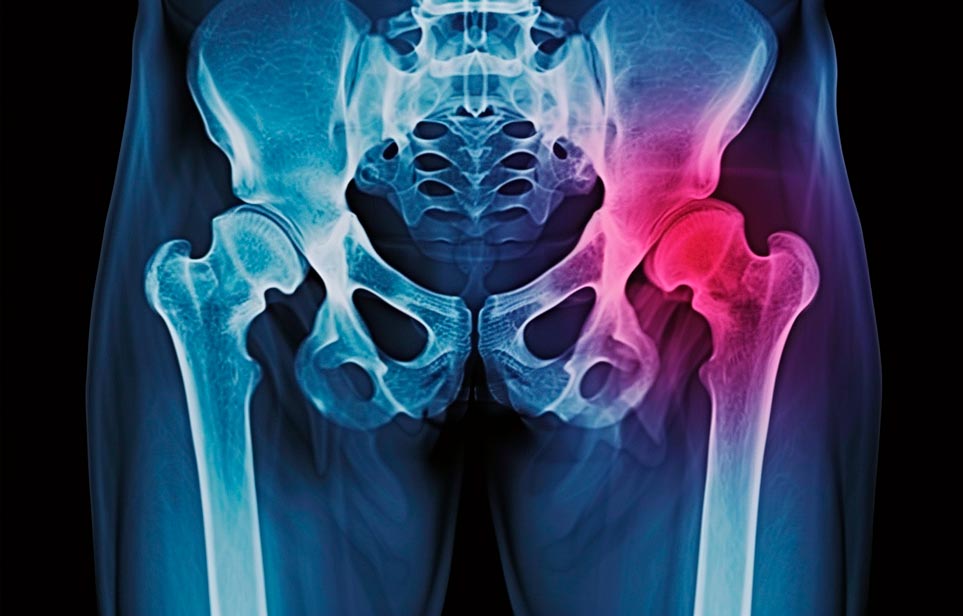

Реабилитация пожилых после перелома шейки бедра в Николаевке

Эффективная и профессиональная реабилитация после перелома шейки бедра в Николаевке осуществляется по демократичным ценам лучшими специалистами современной медицинской клиники «Заботливые люди» с применением персонального подхода к каждому пожилому человеку с такой тяжёлой травмой бедренной кости ноги. В процессе осуществления такой специализированной услуги все наши пациенты имеют возможность получения качественного и достойного обслуживания, эффективного восстановления. Лучший дом престарелых позаботиться о Вашем близком человеке.

Такая травма в большей части случаев возникает у граждан преклонного возраста. При её появлении на протяжении длительного времени сохраняются болевые и неприятные ощущения в области паха, при которых серьёзно ухудшается качество жизни, возникает множество последствий для его жизни и здоровья.